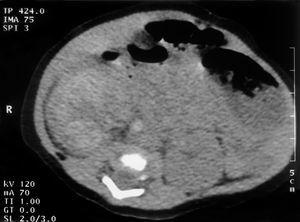

En la analítica destacaba hemoglobina 20,4 g/dl; hematocrito, 63 %; neutrófilos inmaduros/neutrófilos totales, 0,7; creatinina, 96 μmol/l,; AST 159 U/l; creatinfosfocinasa, 3.505 U/l; proteína C reactiva, 25,4 mg/dl. Recibió ampicilina y gentamicina. A las pocas horas presentó hipertensión arterial que necesitó tratamiento farmacológico, con buena respuesta. A las 48 h de vida se detectó una masa en flanco derecho y hematuria isomórfica. La ecografía abdominal mostró un riñón derecho patológico (fig. 1) y el Doppler del riñón derecho era indicativo de TVR (fig. 2). La gammagrafía renal evidenció ausencia de riñón derecho. La tomografía computarizada (TC) abdominal mostró calcificación en la cava infrarrenal (fig. 3). El dímero D fue 4.756 μg/l. La tabla 1 muestra el resultado del estudio biológico de trombosis. Analíticas sucesivas constataron trombopenia (80 x 109/l), incremento de la creatinina (116 μmol/l) y proteinuria (95 mg/h/m2) con normalización posterior. Diuresis conservada. La actividad renina plasmática: 21,5 μg/h/l. No precisó cateterismo umbilical.

Figura 3.TC abdominal: calcificación de la vena cava inferior infrarrenal compatible con trombosis.